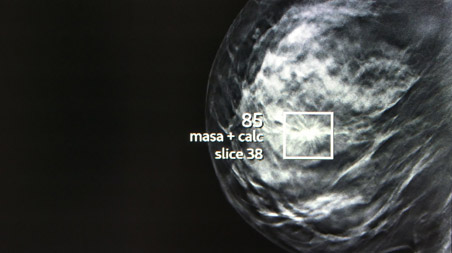

Mammography

Mammography is an imaging technique that uses low-dose X-rays to examine breast tissue. It is the most effective method for the early detection of breast cancer, even before symptoms appear. It allows microcalcifications, nodules and other abnormalities in the breasts to be identified. The procedure is quick, safe and can save lives thanks to early diagnosis. At our centre, we have state-of-the-art technology (tomosynthesis or 3D mammography) to offer you an accurate and comfortable mammogram.

Comprehensive diagnosis of breast pathology

We work with the most advanced Tomosynthesis and Digital Mammography technology, which produces less X-ray radiation and is more sensitive in the early detection of breast cancer. We participate in breast screening programmes.

We also carry out high-resolution studies in breast pathology, such as magnetic resonance imaging and biopsies. All without waiting times.